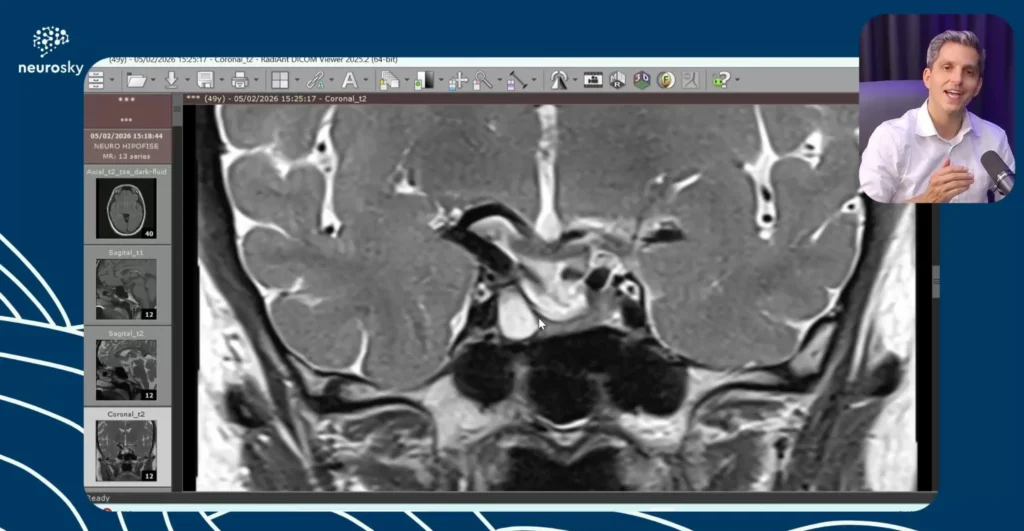

Avaliação RM Hipófise

Nesta nova aula publicada na neurosky, Dr. Tomás Freddi fala sobre “Avaliação RM Hipófise”, uma análise prática e aprofundada de um caso clínico de avaliação…